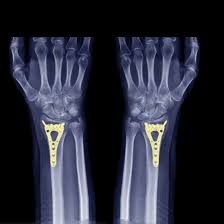

NCCT Right Arm uses X-rays to take detailed cross-sectional pictures of your right arm. The scanner takes multiple images from different angles, showing your arm’s structure from shoulder to fingertips. This helps doctors see breaks, cracks, or other problems clearly. No dye or injection is needed for this scan. It can show even tiny fractures or early signs of bone problems that regular X-rays might miss. The scan checks your bones, muscles, and soft tissues in one go, saving time and giving complete information about your arm condition.